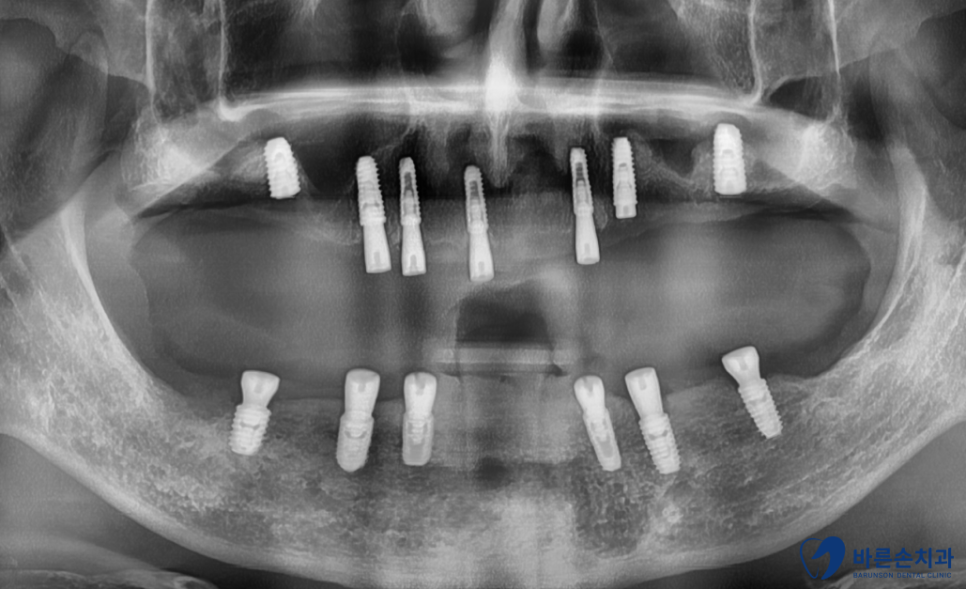

초진 엑스레이

엑스레이 사진으로 보니

잇몸뼈 (빨간 선)가 푹 꺼져서 치아를 잡아주지 못하고 있습니다.

원인은 전부 치석으로 인한 치주병 때문입니다.

최대한 치아를 살리고 싶지만 안타깝게도 전부 살릴 수 없고 발치해야 하네요..

전악 발치, 임플란트 계획을 세우게 되었습니다.

임플란트를 총 13개 식립하고